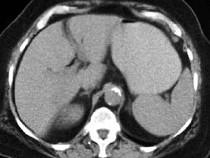

问题 男,30岁,有胆结石病史,近日腹痛、腹胀,CT检查如图,应诊断为 ( )

选项 A.胆石症 B.胆石性肠梗阻 C.肠结核 D.小肠克罗恩病 E.小肠淋巴瘤

答案 B